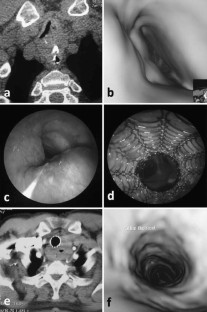

Fig. 1

Fig. 2

Fig. 3

Fig. 4